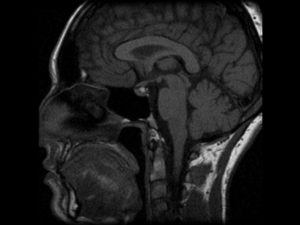

Киста Ратке локализуется между долями гипофиза – передней и задней (аденогипофиз, нейрогипофиз), чаще в зоне турецкого седла. Обычно располагается интраселлярно (в пределах турецкого седла) или супраселлярно (над областью турецкого седла). Главное осложнение – преобразование кисты в доброкачественную опухоль (краниофарингиома), которая формируется из клеток эпителия.

Если предполагается злокачественный характер опухоли, показана консультация онколога. Один из самых информативных методов диагностики – МРТ исследование, которое позволяет дифференцировать кисту, сформировавшуюся в зоне кармана Ратке, от таких патологий, как арахноидальные кисты или аденомы гипофиза (пролактиномы).

На снимке отчетливо видно хорошо отграниченное новообразование кистозной структуры округлой или продолговатой формы иногда с утолщенной стенкой. КТ-томография показывает большую плотность ткани кисты по сравнению с окружающей мозговой тканью.

Киста кармана Ратке при компьютерной томографии характеризуется как кистозное образование селлярнй или супраселлярной локализации, с четкими границами, сниженной плотности. Крупные размеры могут приводить к ремоделированию прилежащих костей.

Магнитно-резонансная томография

Кисты кармана Ратке почти всегда имеют гомогенную интенсивность МР сигнала, в то время как кистозные краниофарингеомы и аденомы с кровоизлиянием имеют гетерогенный сигнал. [9] Уровни жидкости подразумевают кровоизиляние в анамнезе. Хотя кисты кармана Ратке не имеют характерных только для данной нозологии МР признаков. Большинство кист можно отнести к двум группам:

- Кисты кармана Ратке с низкой интенсивностью МР сигнала на Т1 взвешенных изображениях и высокой интенсивностью сигнала на Т2 взвешенных изображениях,

- Кисты кармана Ратке с высокой интенсивностью МР сигнала на Т1 взвешенных изображениях и различной интенсивностью МР сигнала на Т2 взвешенных изображениях

В первой группе содержимое кисты серозное и имеет сигнальные характеристики соответствующие ЦСЖ. Во второй группе содержимое кист богато мукополисахаридами, которые считаются продуктами муцин-продуцирующих клеток в стенке кисты.

Главным методом для обнаружения кисты является магнитно-резонансная или компьютерная томография. Так как это образование похоже на аденому гипофиза и краниофарингиому, то чаще всего необходимо дополнительное введение контрастного вещества. К наиболее важным диагностическим критериям кисты кармана Ратке относятся:

- расположение внутри турецкого седла, или она выходит и за его границы;

- форма – овал, гантель, круг;

- находится между передней и средней долей;

- размер обычно 1-2 см, реже бывают крупные – до 4-5 см, они могут разрушать костные ткани;

- при введении контраста не накапливает его;

- границы четкие;

- однородной структуры;

- не содержит отложений кальция в отличие от опухолей.

На снимке МРТ стрелочками указана киста и аденогипофиз, который всегда деформирован кистой, и киста непосредственно к нему прилегает

Плотность содержимого кисты ниже, чем окружающая ткань, если преобладает жидкостный компонент внутри. При усиленном накоплении белков и мукополисахаридов консистенция становится желеобразной. В редких случаях имеется неоднородность сигнала за счет того, что присутствуют включения жиров, распавшейся крови, слущенного слоя эпителия, который выстилает изнутри кисту.

Окружающая ткань гипофиза может выглядеть более плотной, так как отмечается сдавление его клеток. При аденоме, наоборот, соседние области разрежены, так как максимальная гормональная активность наблюдается внутри опухоли.